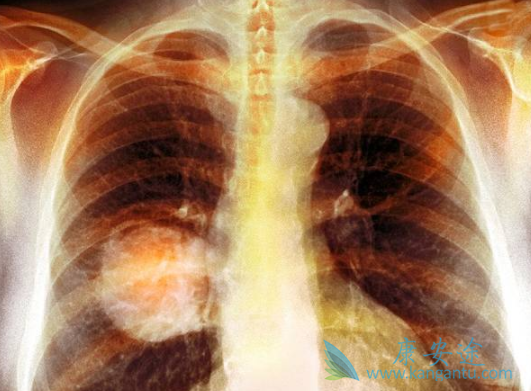

与多西他赛相比,欧狄沃TM (纳武利尤单抗射液, nivolumab injection)在经治非小细胞肺癌患者中生存获益显着,可降低死亡风险32%;无论PD-L1表达与否,所有鳞癌和非鳞癌患者均能获益;有效性及安全性与国际大型多中心二期临床研究(CheckMate-017/-057)结果一致,东西方人群无显着差异。

纳武利尤单抗(纳武单抗)用药信息:用法用量:3mg/kg,两周一次或2 mg/kg,三周一次。适应症:表皮生长因子受体(EGFR)基因突变阴性和间变性淋巴瘤激酶(ALK)阴性、之前接受过含铂方案化疗后疾病进展或不可耐受的局部晚期或转移性非小细胞肺癌(NSCLC)成人患者。